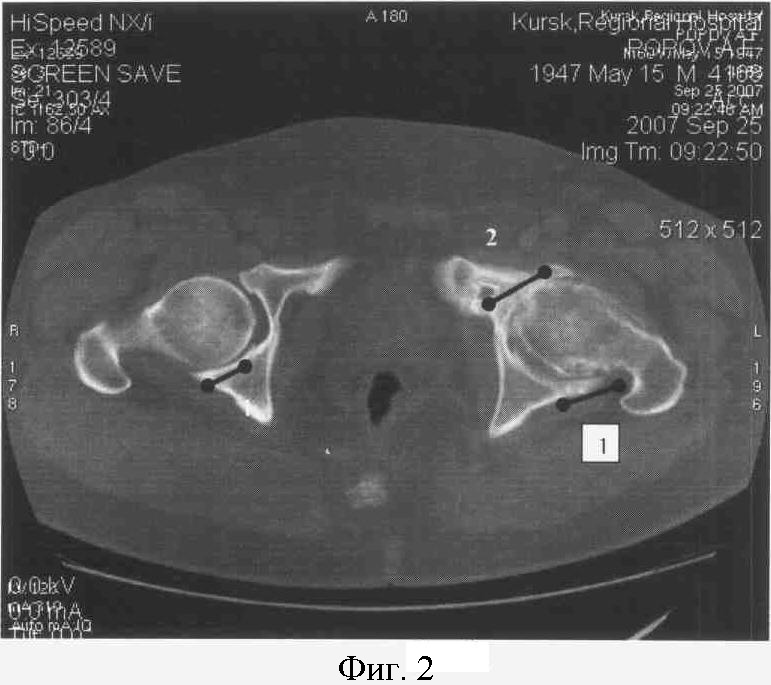

На фиг.4 представлены КТ срезы больного К., 1970 (37 лет).

И/Б 21499/272 Пост.11.10.2007 ОКБ г.Курска.

На фиг.5. представлен КТ срез на уровне верхней трети головки бедра больного К.

Справа: 1-я стадия коксартроза с локализацией участков компрессии в заднем отделе сустава (1).

Слева: 2-я стадия коксартроза с кистевидной перестройкой с локализацией участков компрессии в заднем (1) и переднем отделах сустава (2).